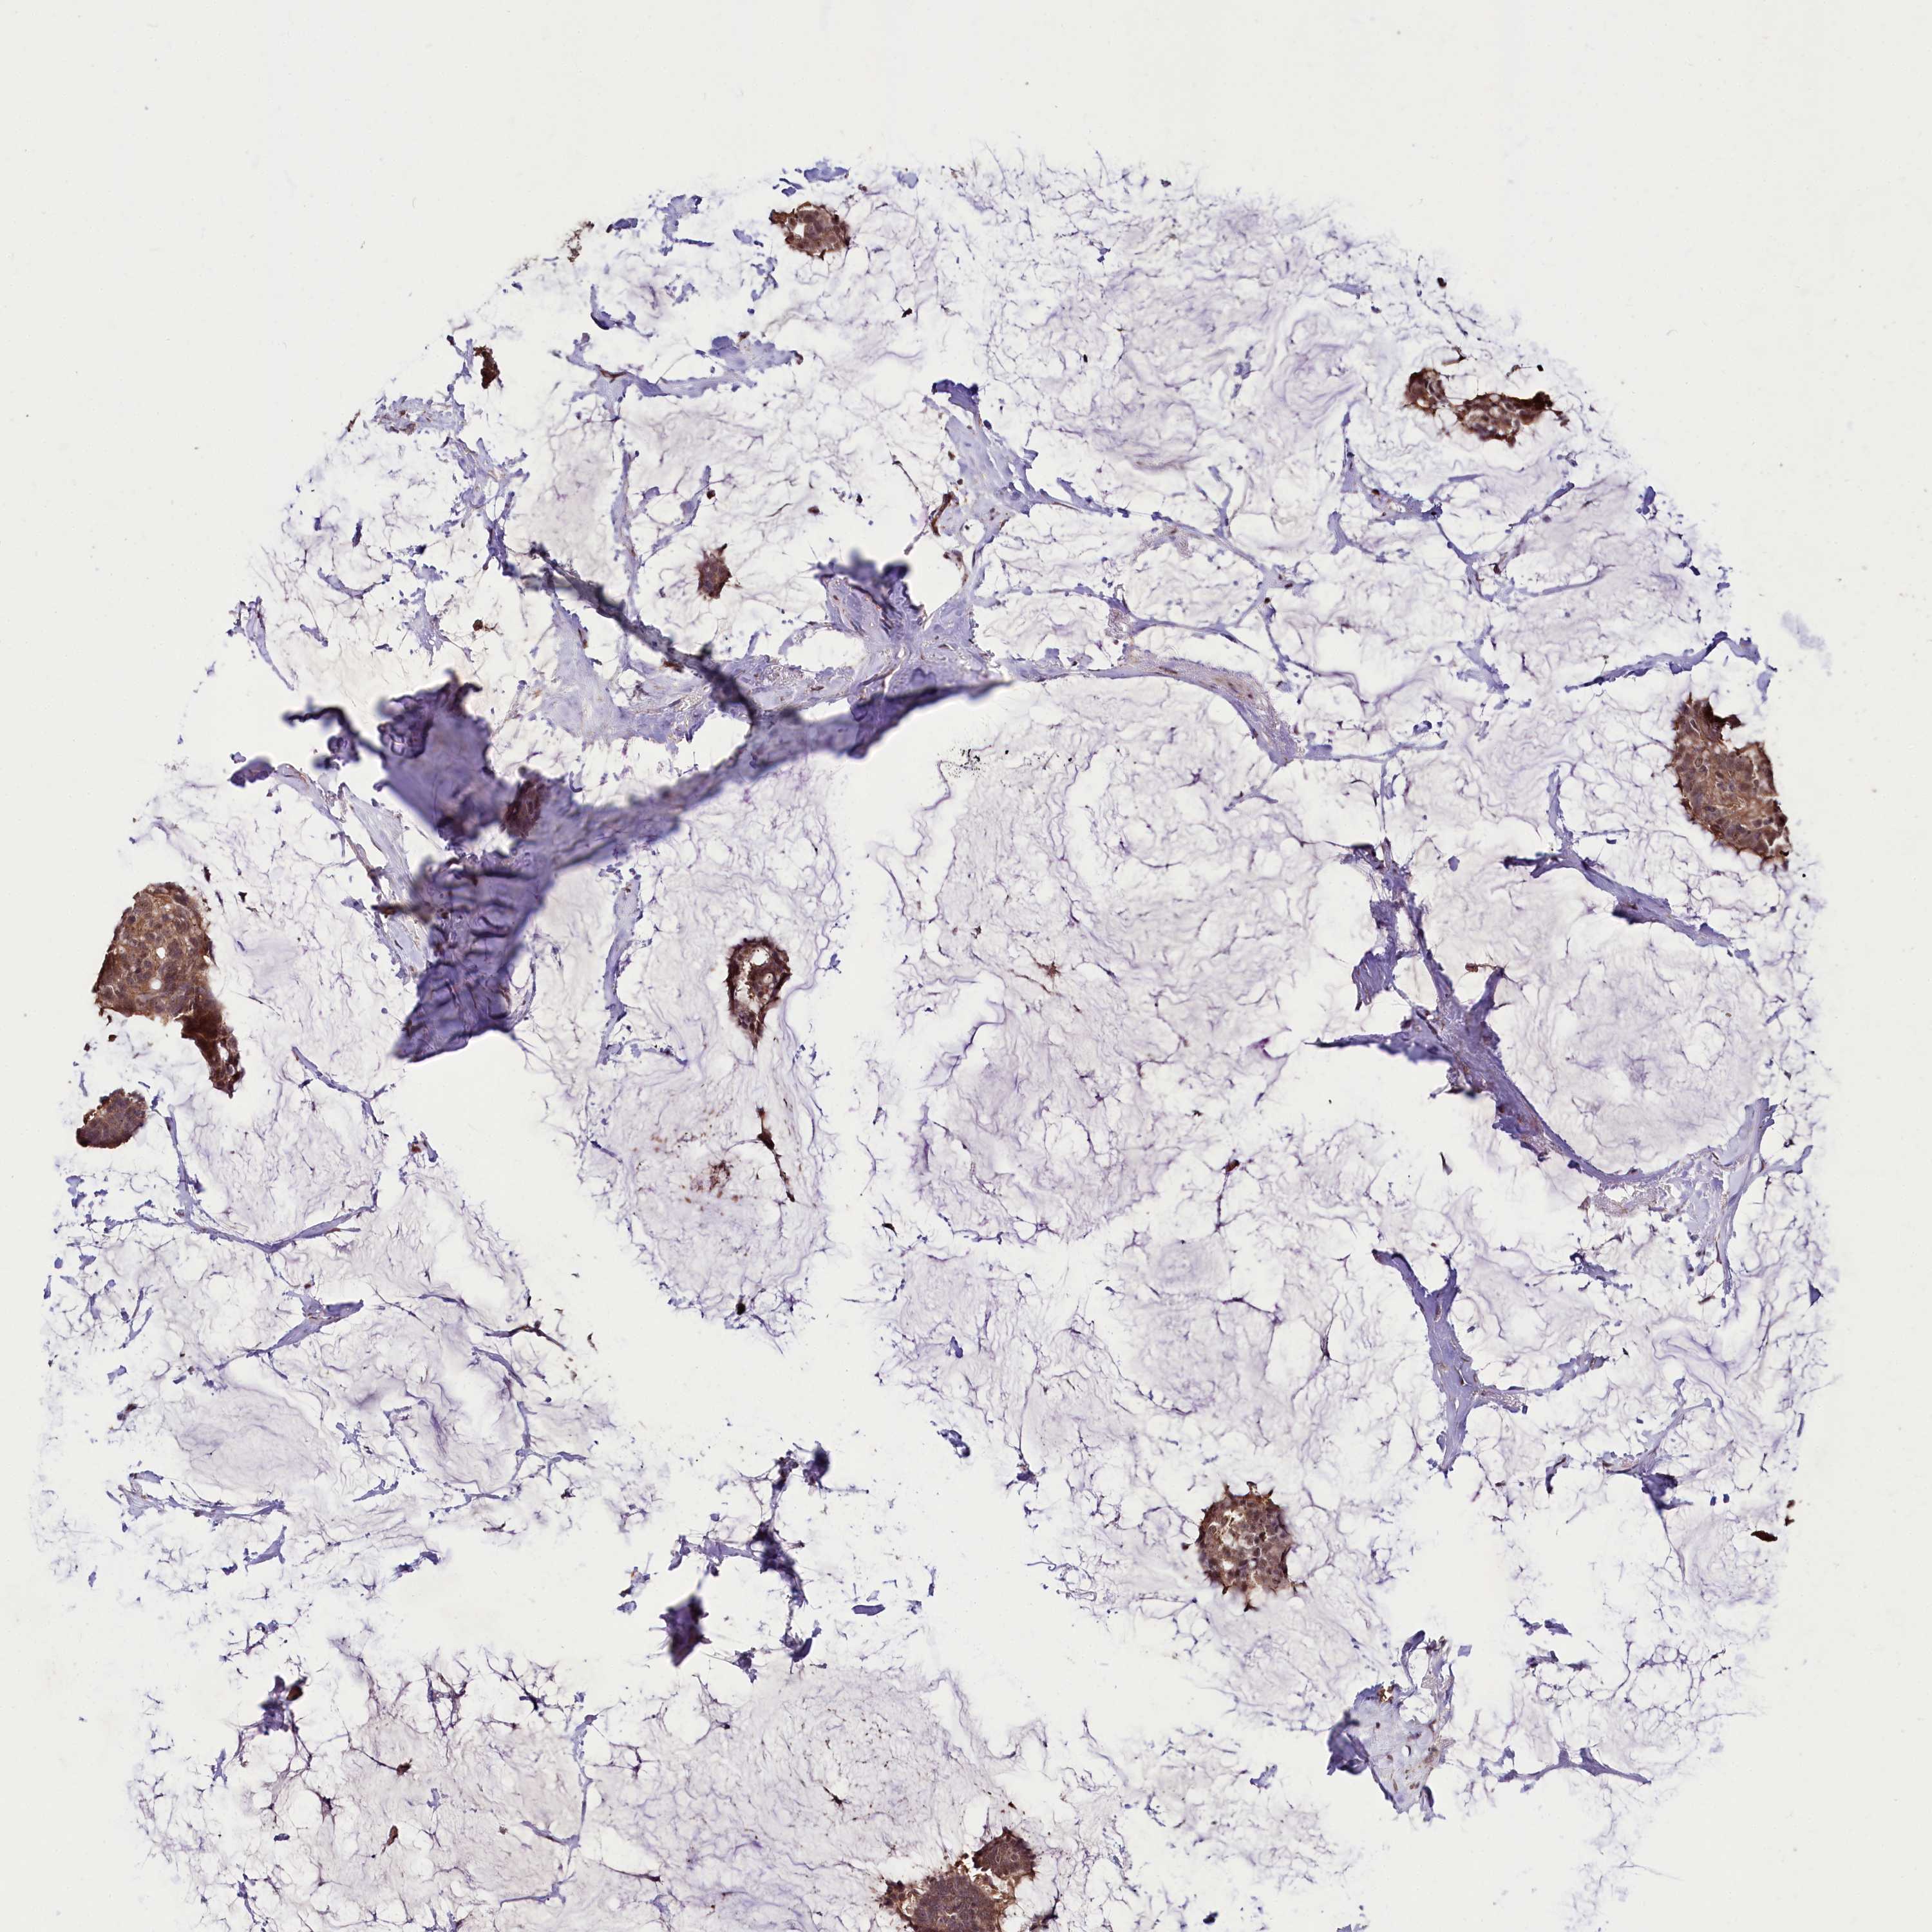

CANCER BREAST CANCER Show tissue menu

BRCA TCGA BRCA VALIDATION PROTEIN EXPRESSION

Breast cancer

Human cancer

Breast invasive carcinoma